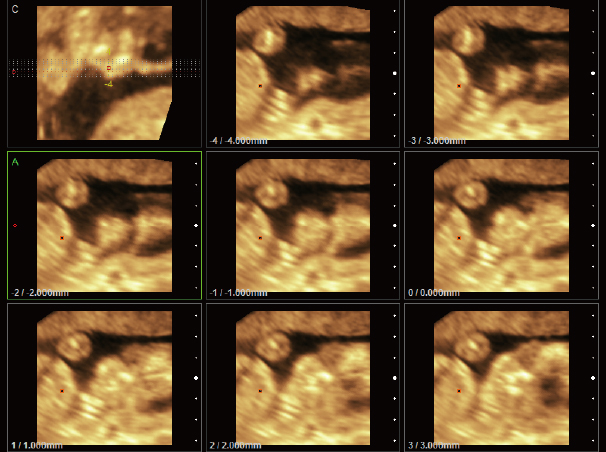

四维,断层成像